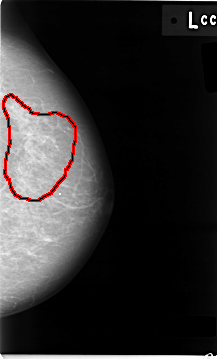

FILE: C_0007_1.LEFT_CC.OVERLAY

TOTAL_ABNORMALITIES 1

ABNORMALITY 1

LESION_TYPE CALCIFICATION TYPE AMORPHOUS DISTRIBUTION REGIONAL

ASSESSMENT 5

SUBTLETY 5

PATHOLOGY MALIGNANT

TOTAL_OUTLINES 1

BOUNDARY